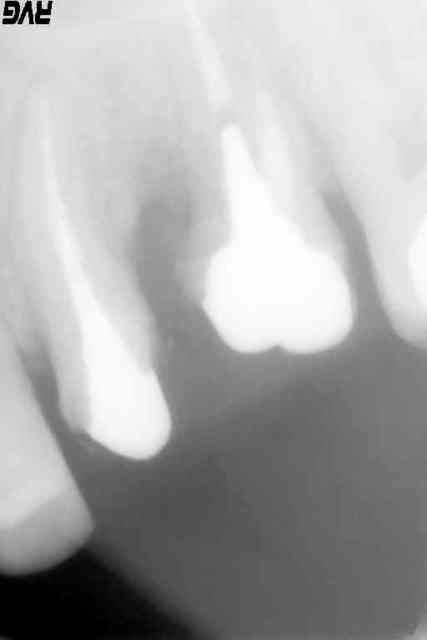

j'ai fait mais il reste la racine DV

Pas de pb.